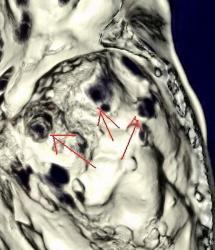

Метастазы в костях основания черепа.

Женщина средних лет с клиникой невралгии тройничного нерва справа. На КТ были выявлены округлые очаги деструкции в костях основания черепа (средней черепной ямки).

Наблюдение Nela.